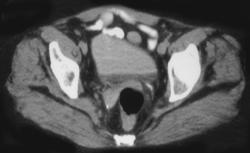

Obstructing Left Distal Calculus in Ureter